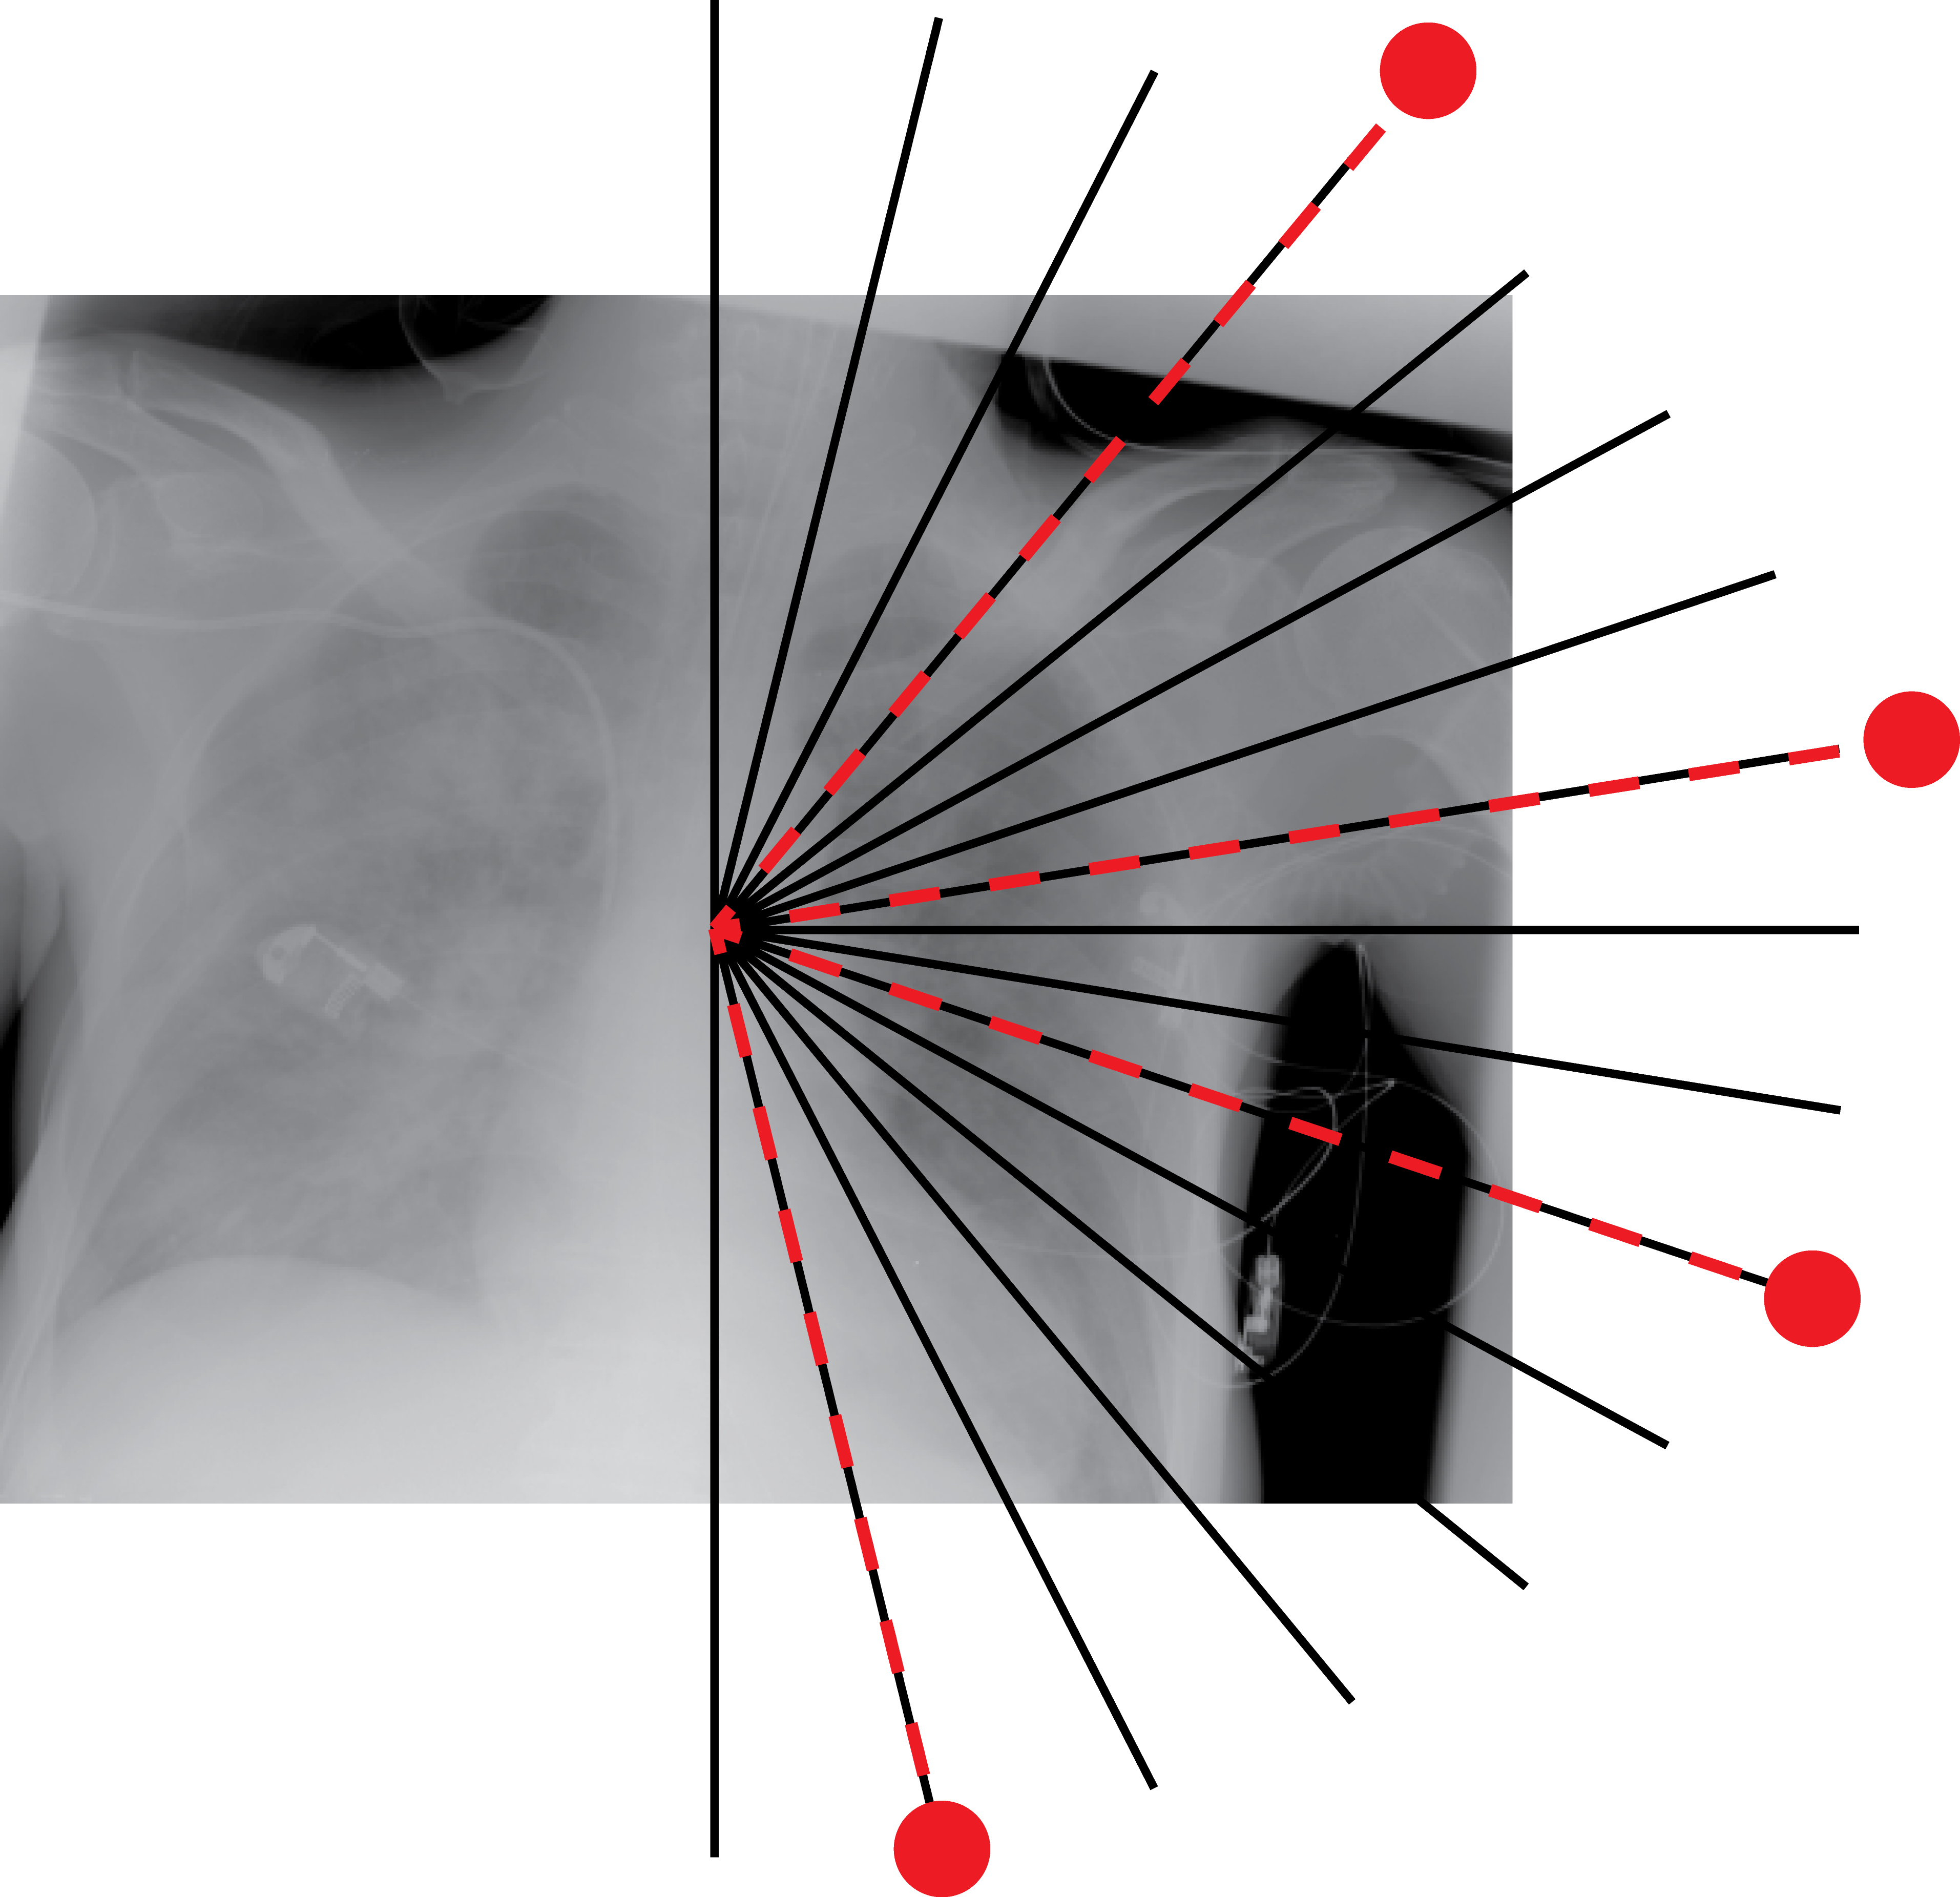

Radon barcodes are binarized versions of Radon projections. To create the optimal Radon barcodes (barcodes that are highly expressive to tag digital images in a unique way such that they can be retrieved easily), one has to find the optimal projections. Since we are trying to find projections, we should find a fitness function that guides micro-DE in the right direction. If the projections are good (compared to all other possible combinations), then image reconstruction using these projections should yield smaller error compared to all other combinations. Figure 3 shows for the chest x-ray that the 4 best projections by examining all 1820 combinations when 16 equidistant projections are available.

In this section, we report two series of experiments. The first one verifies the correctness or reliability of the micro-DE algorithm to find optimal projections compared to an exhaustive search when we are looking for 4 optimal projection angles out of 16 equidistant angles. In the second experiments, we still provide the results for exhaustive 4/16 selection but examine the evolutionary approach to get 4/180 and 8/180 to investigate the reconstruction accuracy of the micro-DE via correlation of the input image and the reconstructed image using 4/16 (exhaustive), 4/180 (micro-DE) and 8/180 (micro-DE). To conduct the experiments we used 50 images from IRMA dataset [34, 35], a benchmarking collection of 14,400 x-rays images. We selected 10 random classes out of 58 classes, and for each class, we randomly drew 5 images to be used in our experiments. Figure 4 shows the images we have used.